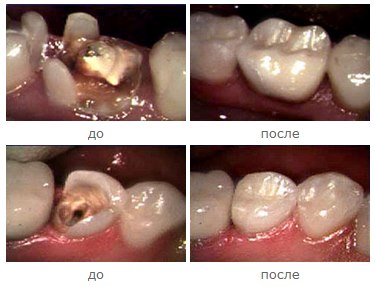

Вкладка Инлей

Вкладка Инлей используется при восстановлении дефектов, расположенных в зоне фиссур, а также боковых поверхностей зуба при условии, что сохранены бугры коронковой части зуба.